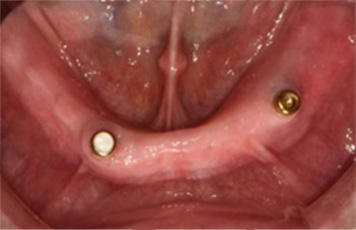

틀니는 환자 본인이 탈부착이 가능한 가철성 보철물입니다.

잇몸뼈 상태, 전신질환, 비용 등으로 임플란트가 힘든

환자들에게 많이 시술되고 있습니다.